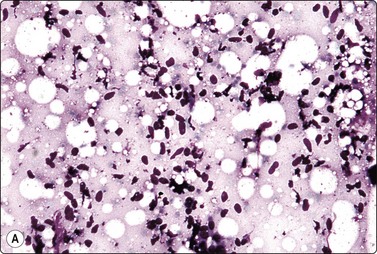

image image image

Fig. 7.19 Fat necrosis

(A) Postoperative fat necrosis. Necrotic tissue, debris and macrophages; fragment of adipose tissue upper right (MGG IP); (B) Fragments consisting of altered adipocytes, macrophages and fat droplets (MGG, IP); (C) Several multinucleated histiocytes with foamy cytoplasm (MGG, HP).

Criteria for diagnosis

A ‘dirty’ background of granular debris, fat droplets and fragments of adipose tissue,

Foamy macrophages, multinucleated giant cells and adipocytes with bubbly cytoplasm,

Chronic inflammatory cells,

Absence of epithelial cells.

Postoperative changes in response to prior surgical excision or biopsy give similar findings. Fat necrosis is always in the differential diagnosis of nodules in scars or chest wall after surgery, particularly mastectomy. Vigorous or repeated palpation of breast tissue or previous aspiration of the site can result in the same changes. The aspirate is usually scanty, sometimes of oily fluid, and consists mainly of fat with some foamy macrophages or altered, vacuolated adipocytes and multinucleated histiocytic giant cells. The untidy background of granular debris represents the actual necrosis and is the most specific diagnostic feature (Fig. 7.19A,B).